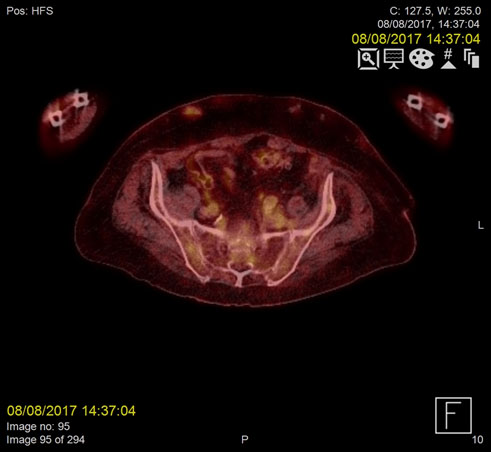

Repeat F18-FDG PET- CT images acquired two months later demonstrated complete resolution of the IMV and SMV thrombi (Figure 1-2).

Figure 1b. Resolution of infected thrombus in the IMV two months post-treatment